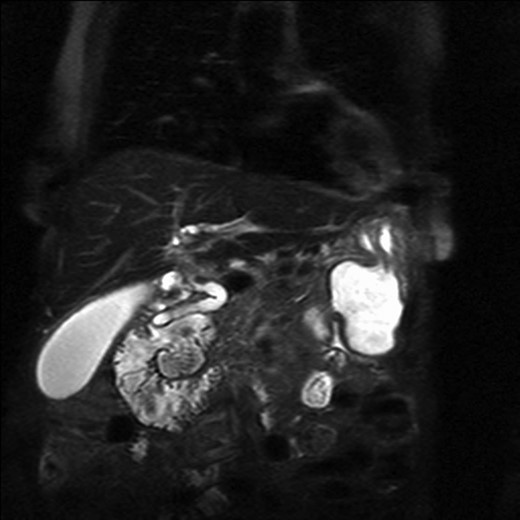

The patient underwent an MRCP which demonstrated mild distension of the gallbladder with several calculi. There was intra- and extra-hepatic biliary dilatation to the level of the ampulla. A very large fluid and air filled periampullary duodenal diverticulum measuring ~8 cm in the long axis was also noted (Figs 1–3). This finding was unchanged compared to a CT study from 6 months previously. The CBD was dilated to the level of this diverticulum and the cause of the patient’s biliary dilatation and obstruction. Interestingly, an unusual appearance to the kidneys was recorded with multiple microcystic changes in both kidneys, which is typically reported in patients with lithium induced renal disease. A gastroduodenoscopy revealed a large periduodenal diverticulum in D2 (Fig. 4).